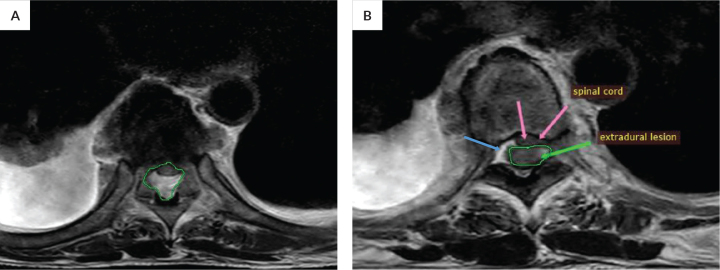

In rare cases with no clinical practice guidelines available, the approach heavily relies on small studies, reports, and professional experience based on sound clinical judgement from available data. We present a case of a 52-year-old male radiation technologist with a 5-year history of pancytopenia diagnosed with radiation-induced marrow aplasia after presenting with bilateral lower extremity weakness and numbness. MRI revealed spinal EMH along T3 to T12. He was given steroids and radiation therapy (RT) of 18Gy in 10 fractions with improvement in sensory status at 4th session of RT and was discharged with steroid on tapering and maintenance of eltrombopag. BM aplasia following chronic low-level radiation exposure results from the accumulation of cytogenetic abnormalities over time. EMH is a compensatory mechanism for BM aplasia, the diagnosis of which is established by MRI. In spinal EMH, transverse myelopathy occurs from spinal cord compression (SCC). As of writing and with our literature-search, spinal EMH has never been reported in patients with aplastic anemia or radiation-related BM aplasia. With the paucity of available data, there is currently no specific guidelines in managing BM aplasia from radiation and consequent SCC. However, as with most cases of SCC, radiotherapy, steroids, and surgical decompression are viable options. This case report will add to the very small pool of information on EMH from radiation-induced BM aplasia and its approach to management especially in this rare, never-before-reported presentation.